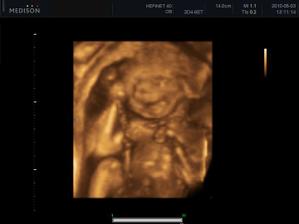

Náš zázrak